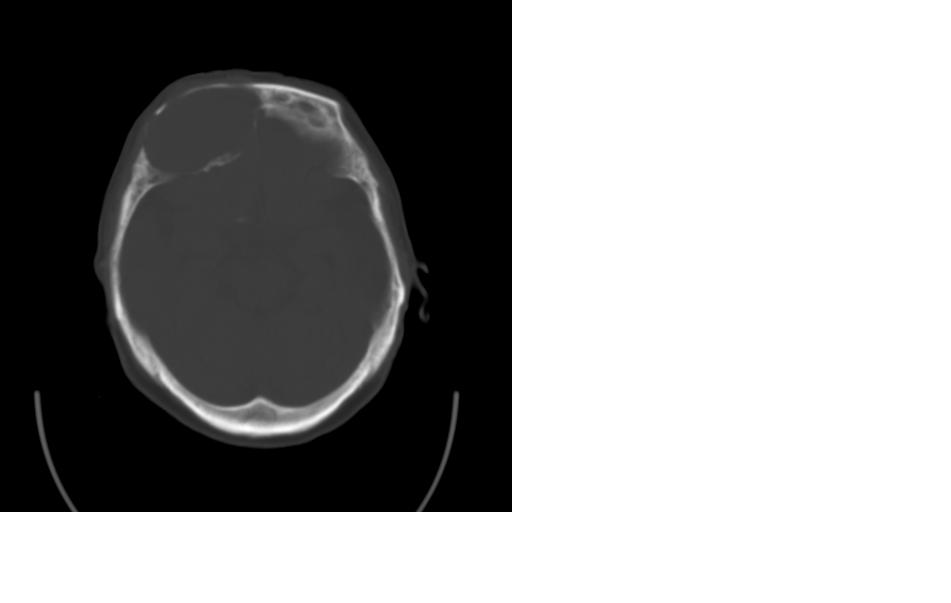

女,77岁,渐进性突眼2年,无其他明显症状

病变位于起源于右侧筛窦,右侧眼球受压移位,右侧大脑半球额叶白质受压塌陷,水肿不明显.额骨呈压迫性骨质吸收变薄.考虑脑膜瘤,建议增强吧

右侧额部软组织密度肿块,界限不清,明显向前下方增长,占位效应明显,内见钙化,局部颅骨明显吸收.考虑:右额叶脑膜瘤.建议:增强

右额窦粘液囊肿,向前累及筛窦并进入眼眶使眼球前突;向下进入颅内右额叶脑质及侧脑室受压

病变应起源于右侧额窦/或额骨板障,肿块周围骨包壳尚完整,呈膨胀挤压改变,右侧眼球受压移位,右侧大脑半球额叶白质受压塌陷,水肿不明显.考虑为良性病变,骨纤维瘤/或骨嗜酸性肉芽肿? 建议增强吧

额骨右侧呈明显膨胀性骨质破坏,内外板明显变薄.考虑骨巨细胞瘤或动脉瘤样骨囊肿的可能性大。

定位:来源右额窦。定性:良性占位—额窦黏液囊肿。理由1、病灶中心位于右额窦区,侵及筛窦并向下向前压迫眼球2、骨质呈膨胀性改变,骨质弓形变薄但骨壳完整,如为恶性骨质应为侵蚀性破坏3、黏液囊肿好发于筛窦、额窦。